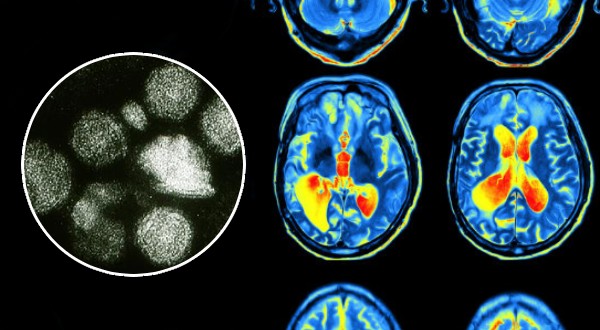

সংক্রামক রোগের হাত থেকে বাঁচার সবচেয়ে কার্যকর উপায় অবশ্যই ভ্যাকসিন। আবার একবার সংক্রমণ হয়ে গেলেও সেই রোগের বিরুদ্ধে প্রতিরোধ ক্ষমতা গড়ে ওঠে। তখন নতুন করে সংক্রমিত হওয়ার সম্ভাবনা থাকে না বললেই চলে। কিন্তু সবসময় এই হিসাব মেলে না। বিশেষ করে যখন মানুষের প্রতিরোধ ক্ষমতা একেবারে শূন্যে নেমে আসে। আগের সমস্ত সংক্রমণের স্মৃতি ভুলে যায় শরীর। এমনকি আগে নেওয়া ভ্যাকসিনের স্মৃতিও হারিয়ে যায়। না, স্মৃতি বলতে ঘটনাটি মনে থাকার কথা নয়। শরীর আর সেই জীবাণুদের চিনতে পারে না। ‘ইমিউন অ্যামনেসিয়া’ (Immune Amnesia) নামের এই সমস্যাকে ঘিরে রীতিমতো চিন্তিত বিজ্ঞানীরা। আর এর জন্য দায়ী অত্যন্ত সাধারণ একটি রোগ, হাম (Measles)।

দীর্ঘদিন ধরেই চিকিৎসকরা সন্দেহ করেছিলেন, বায়ুবাহিত ভাইরাস হলেও হামের কারণে শুধু ফুসফুস আক্রান্ত হয় না। তাহলে কোন কোন অংশ আক্রান্ত হয়? ২০০২ সালে জাপানি বিজ্ঞানীদের একটি দল সেটাই পরীক্ষা করে দেখতে চায়। আর তাতেই ধরা পড়ে, হামের ভাইরাস সবার আগে আমাদের টি-লিম্ফোসাইট কোষ নষ্ট করতে শুরু করে। এরপর নতুন করে যে টি-লিম্ফোসাইট কোষ তৈরি হয়, তা হামের বিরুদ্ধে প্রতিরোধ ক্ষমতা নিয়েই জন্মায়। কিন্তু পূর্ববর্তী সংক্রমণের স্মৃতি হারিয়ে যায়। অবশ্য ২০০২ সালের এই গবেষণা অনেকেই গুরুত্ব দিয়ে দেখতে চাননি। ঠিক ১০ বছর বাদে, ২০১২ সালে বিষয়টি নিয়ে আবার গবেষণা শুরু হয়। এর মধ্যেই ২০১৩ সালে নেদারল্যান্ডে হামের মহামারী দেখা দেয়। ফলে গবেষণার নমুনা সংগ্রহ করাও সহজ হয়। জাপানি বিজ্ঞানীদের সিদ্ধান্তই প্রমাণিত হয় শেষ পর্যন্ত।